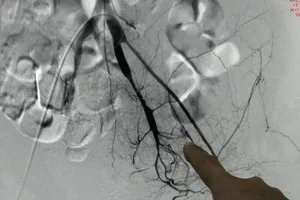

Thả 9 vòng xoắn kim loại cứu bệnh nhân ung thư vòm hầu xuất huyết nguy kịch